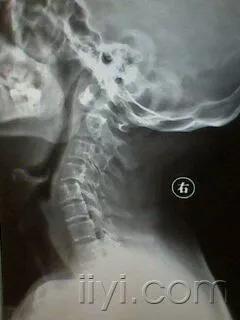

颈椎生理曲度反弓